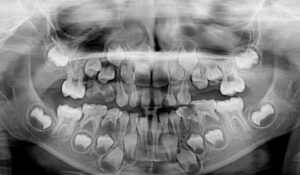

Мы ждем и радуемся появлению новых зубиков у смешных беззубых младенцев, но на самом деле, зубы закладываются еще на эмбриональной стадии и человек рождается уже с комплектом зубов. Даже с двумя комплектами: молочные и постоянные. Но ни одного зуба нет на месте – все они спрятаны в челюсти до поры до времени.

Сколько у человека молочных зубов? 20 штук, все они вырастают лет до 8 и потом потихонечку выпадают и сменяются постоянными зубами.

А почему вообще возникла необходимость в молочных зубах? Дело в том, что детская челюсть еще очень маленькая и взрослый размер зубов для нее слишком велик… и тяжел.

Помните, какой трогательный «заборчик» на новеньких постоянных зубах у детишек?